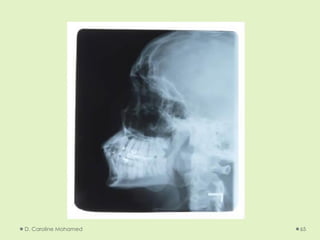

D. Caroline Mohamed 64